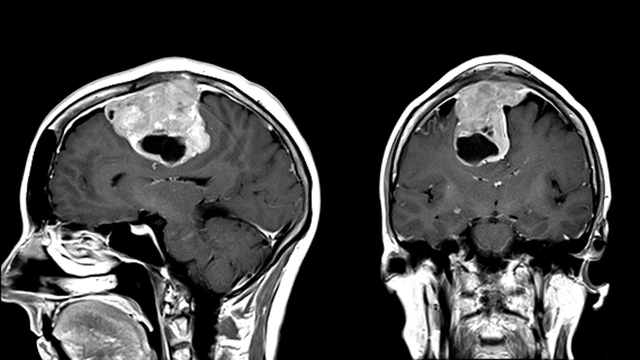

:format(webp)/tim_hieu_ve_vai_tro_cua_chup_mri_u_mang_nao_trong_chan_doan_benh_c61af8a869.jpg)

Chụp cộng hưởng từ (MRI) đóng vai trò quan trọng trong chẩn đoán và đánh giá u màng não. Vậy chụp MRI là gì? Vai trò của chụp MRI u màng não trong chẩn đoán bệnh như thế nào? Trong bài viết hôm nay, Nhà thuốc Long Châu sẽ phân tích những ưu điểm của MRi trong chẩn đoán bệnh u màng não nhé!